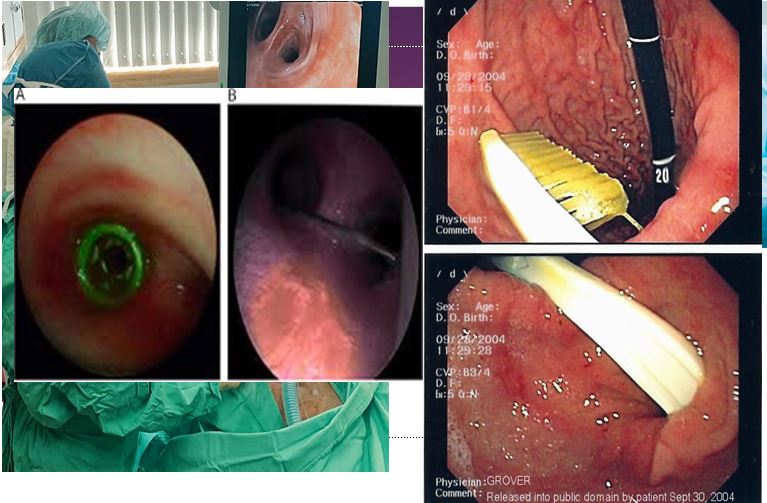

وهنا صور لابتلاع البطاريات الخطيرة جدا...